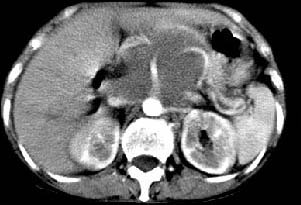

胰腺受压前移,胰管扩张,应为腹膜后占位,病灶密度不均,有低密度坏死区,强化扫描强化不明显腹腔干动脉受侵,考虑腹膜后恶性占位

肝胃之间、肝十二指肠韧带,胰头后、腹主a周围,融合而成团块状影,包绕血管[腹腔干、肠系膜上动脉,腹主动脉],胰腺前移后缘分界欠清,与肝胃分界清,肿块未见明显强化,肝右叶后段小囊肿。

主动脉-胰腺间隙可见巨大分叶状软组织肿块影,包绕腹主动脉、腹腔干及其分支、腔静脉等大血管,增强呈无明显强化,临近脏器明显受压移位,增强示有分界。肝右叶可见局限性低密影,边缘清楚。

影象表现:平扫,首先可见胃壁明显增厚,内外边缘清晰,外缘光滑,内边缘不归整,同时胃腔明显缩小。

再看从肠系膜根部到胰腺后主动脉及上腔静脉周围可见相连的较大的软组织肿块影,形态不规则,呈明显

的大小不等的分叶状,其中密度较均匀但其中可见条状低密度区,肿块边缘比较清晰周围的小肠受压移位

明显且堆积。

增强所见,腹腔动脉,肠系膜上动静脉被肿块包绕,结合平扫的条状低密度区恰好位于血管周围,较大的

肿块强化不明显(遗憾的是没有标上ct值)但胃壁强化的十分明显。